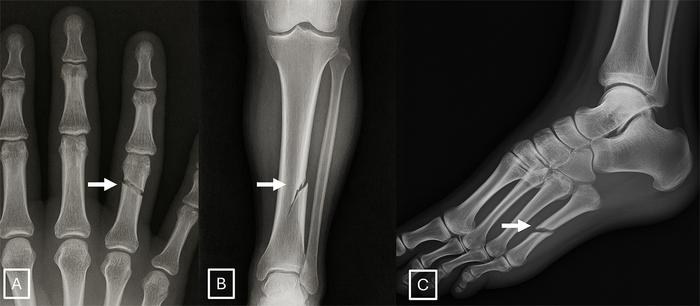

Badacze zidentyfikowali przy okazji charakterystyczne cechy fałszywek medycznych. Sztucznie wygenerowane obrazy często są "zbyt doskonałe": kości są nienaturalnie gładkie, kręgosłupy proste, płuca symetryczne, a wzory naczyń krwionośnych nadmiernie regularne. Fałszywe złamania bywają wyjątkowo czyste i ograniczone do jednej strony kości.